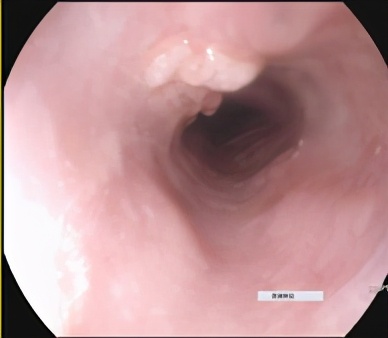

胃镜示:1、距门齿28-31cm处可见一大小约35X15mm的食管肿物。

治疗前胃镜(2020.7)